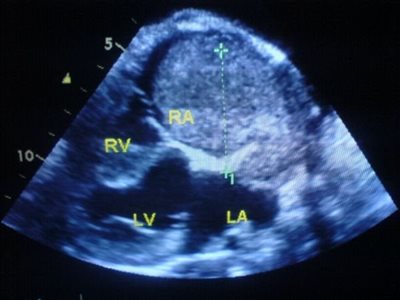

Occluder in a PDA

Caro Laithwaite VN

Rare Heart Tumour in a ...